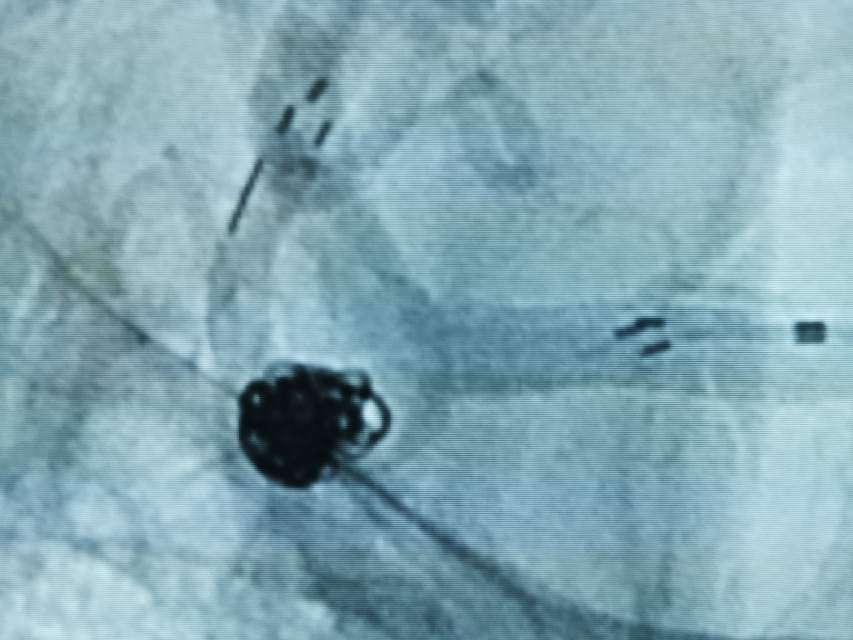

患者大年初一颅内动脉瘤破裂,查出多发颅内动脉瘤,大年初一栓塞破裂的大脑中—豆纹动脉动脉瘤,另外一个对侧的大脑中动脉分叉部动脉瘤形态不规则,顶端有明显的小泡,存在随时破裂的高风险,决定给予支架辅助栓塞术